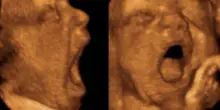

Più il feto sbadiglia nel grembo materno, meno peserà alla nascita

Anche prima della nascita, i feti sbadigliano. E la frequenza di questi sbadigli potrebbe offrire indicazioni sul loro benessere. È quanto emerge da …